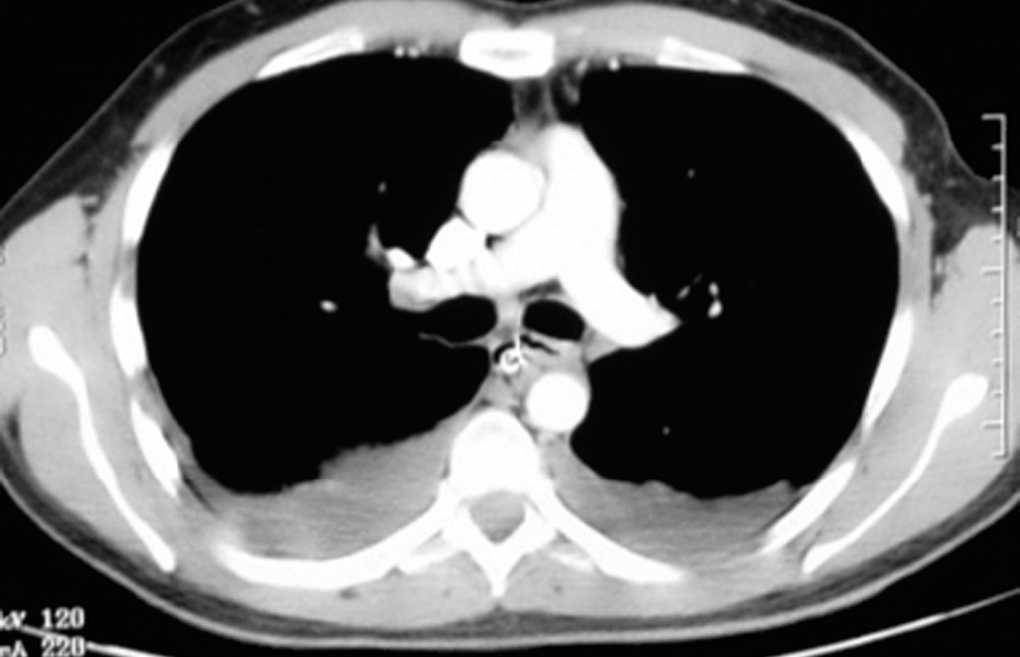

La MND es una entidad poco frecuente, con alrededor de una veintena de casos3,4 descritos en las principales series de la bibliografía. La formación de un absceso en la región bucofaríngea como consecuencia de una infección dental o amigdalar puede desembocar en la formación de una MND. Es un cuadro clínico grave, con una elevada mortalidad incluso actualmente a pesar de los antibióticos de amplio espectro y del desarrollo de la cirugía y de las unidades de cuidados intensivos2,3,6. Su sospecha es fundamental para un diagnóstico temprano, que suele realizarse básicamente mediante la tomografía computarizada8 donde se visualiza la colección líquida, a veces con aire ectópico indicativo de la flora bacteriana anaerobia (fig. 1). La extensión del absceso bucal o cervical hasta el mediastino se comprende puesto que existe una comunicación anatómica a través de los planos de las fascias de los músculos cervicales; además, el mediastino en su parte superior no posee ningún techo cerrado que lo mantenga aislado del cuello. A todo esto hay que añadir la presión intratorácica negativa que facilita, junto con la acción de la gravedad, el descenso de la infección hacia la región mediastínica2. Ante el diagnóstico de una MND hay que actuar inmediatamente con cobertura antibiótica de amplio espectro, ya que suele estar presente una flora mixta polimicrobiana6,11. Actualmente está en discusión el procedimiento quirúrgico en la MND. Algunos autores defienden el drenaje del absceso abordado mediante cervicotomía y toracotomía4,7-9 basándose en la elevada mortalidad de esta afección. Sin embargo, otros autores consideran que un abordaje torácico transcervical10 puede tener un buen resultado, como es el caso que describimos (fig. 2). El mediastino es un compartimiento cerrado, limitado por las pleuras, que lo separan de las cavidades pleurales, pero comunicado cranealmente con la región cervical. Así, el pus procedente del absceso orofaríngeo desciende por el mediastino labrando un camino y permaneciendo estanco siempre que las pleuras mediastínicas no se rompan. Puede haber un derrame pleural reactivo a la mediastinitis (estéril), como en nuestro caso. De este modo es posible el drenaje con facilidad del absceso de una MND mediante la vía transcervical. En el seguimiento hay que atender a la cantidad de líquido drenado y es útil la realización de una tomografía computarizada para una evaluación de control. Progresivamente el tubo torácico se va retirando a medida que cesa el drenaje. A veces conviene realizar lavados con suero fisiológico o con una solución de antiséptico diluido para evitar la obstrucción del tubo. Una vez que los cultivos del drenaje son negativos y que el débito del tubo es escaso, se procede a su retirada. Las radiografías simples de tórax diarias informan de si hay derrame pleural, qué cantidad, si aumenta y, junto con la analítica y la clínica, se podrán realizar otras opciones terapéuticas como la toracotomía con desbridamiento amplio en caso de ser necesario.

Fig. 2. Tomografía computarizada de tórax donde se observa la colección purulenta paraesofágica y subcarinal.